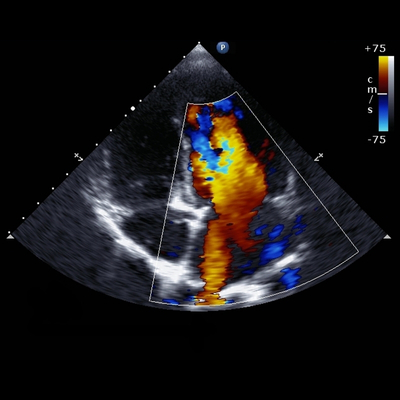

An ultrasound is more like a short video that captures clear images of soft tissues, blood flow and shows if lumps are solid or filled with fluid. Ultrasound shows movement and function, going well beyond capturing structure.

Ultrasound scans are quite different because our sonographer will need to steadily run the probe over the area being scanned. They interpret what they see in real time and decide what to examine more closely, while capturing video and stills at various angles to confirm findings. This process requires careful attention, often involves changing positions to get the clearest view, and in some cases, direct input from a radiologist. This means the scan can take from 15 minutes to 45 minutes, and sometimes longer.